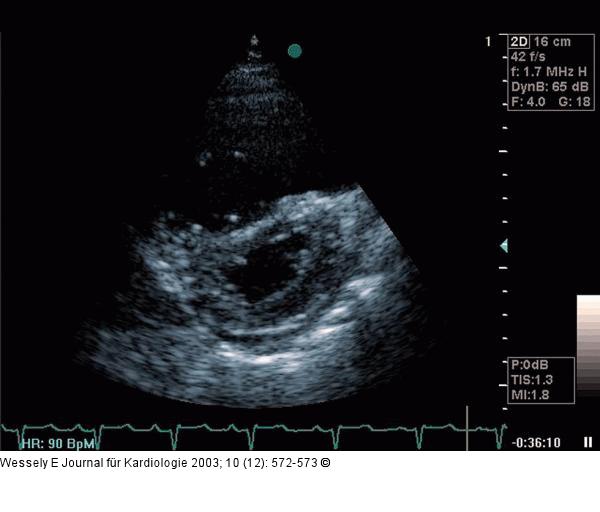

Abbildung 2: Pulmonale Hypertonie Parasternaler Querschnitt: Vergrößerung des rechten Ventrikels mit Septumabplattung und D-Form des Linksventrikelquerschnittes. |

Abbildung 2: Pulmonale Hypertonie

Parasternaler Querschnitt: Vergrößerung des rechten Ventrikels mit Septumabplattung und D-Form des Linksventrikelquerschnittes. |